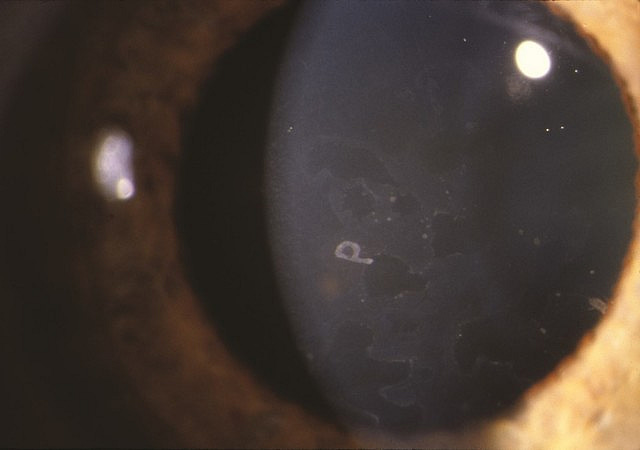

Photo: Wells RG. Diagnostic Imaging of Infants and Children; 2015.